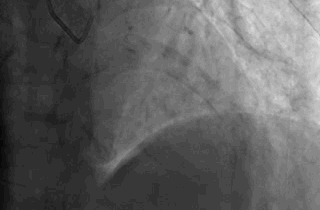

很快,我被确诊急性广泛前壁心肌梗塞。

“心脏左前降支开口位置几乎全被堵了。”

前降支血管

负责左心室的大部分收缩功能。

如果这条血管被堵住了,随时可能发生晕厥、恶性心律失常、心跳骤停猝死。

这条血管被堵住后,心脏就像被扼住了一样没法收缩,

没了血氧供给,心脏前壁范围出现大面积梗死,也可以理解为,心脏窒息了。